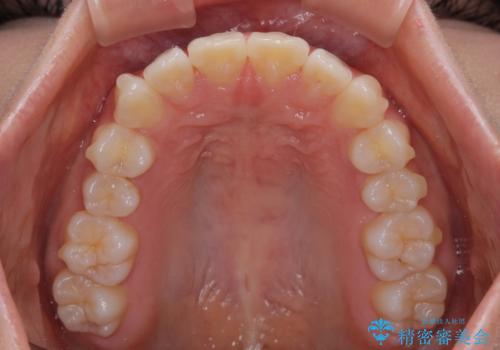

- 上の前歯の隙間を気にして来院された患者様です。

インビザラインにより、上下の歯列を側方に拡大しつつ、前歯の隙間を閉じていくこととしました。

隙間の原因は強い咬合力や舌の突出癖、小帯の異常付着などがありますが、舌のトレーニングをしっかりと行いながら、装着時間を遵守して装着していただいたおかげで、スムーズに治療を終えることができました。